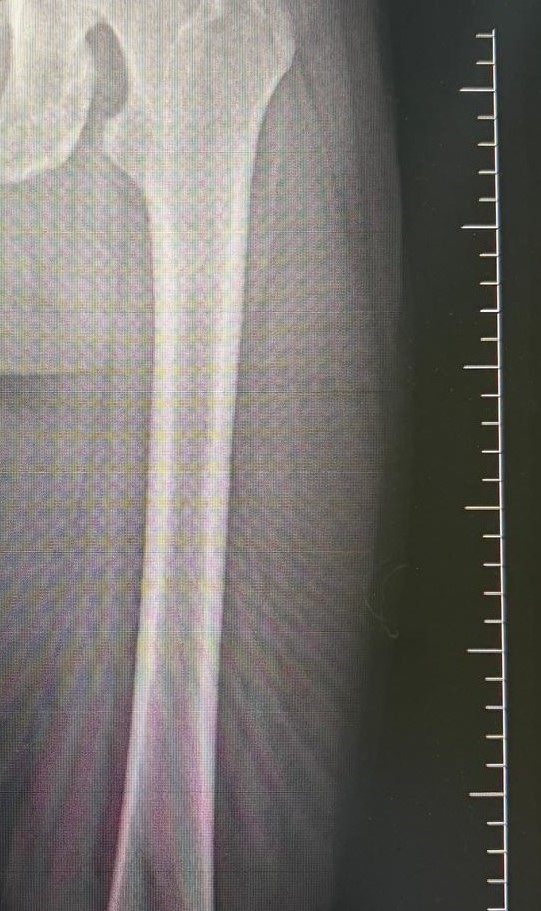

Ameliyat aşamasının ardından gerçekleşen süreci tek tek dile getiren Ortopedi ve Travmatoloji Uzmanı Prof. Dr. Mahmut Argün, "Hastamız 1.58 boyunda olması nedeniyle sürekli boyunun kısalığından dolayı hem fiziksel hem de bedensel rahatsızlıkların olduğunu dile getirdi. Israrla boyunun uzatılmasını bizden talep eden hasta 2 aşamalı olunması gereken muayeneyi 1 aşamalı olmasını istedi. Sol tarafından başlayarak hem femur hem de tibia 5 ila 6 santimetre arasında uzatmayı planladık. Hastamızı ameliyata alıp bu işlemleri gerçekleştirdik. Hasta şuanda uzatma işlemlerinin yapılabilmesi için malzeme yerleştirme aşamasını gerçekleştirdik. Ameliyattan 10 gün sonra uzatma işlemlerini başlayacağız. Uzatma işlemleri yaklaşık 60 gün sürecek. Uzatma işlem süreci geçtikten sonra işlemi durdurup kaynaması için 2-3 ay bekleyeceğiz. Ardından ise hastanın üzerinden malzemeleri yaklaşık 150-200 gün arasında çıkaracağız. Bu tarz işlemler meşakkatli ve özen isteyen ameliyatlar" diye konuştu.

Uzama sürecinde her gün 1 milimetre olmak üzere kurulan mekanizmanın başladığını dile getiren Ortopedi ve Travmatoloji Uzmanı Op. Dr. Necip Özateş, "Her gün 1 milimetre olmak üzere, üzerindeki mekanizma üzerinden hem uyruk kemiği hem kaval kemiği uzatılmaya başlıyor. Hem bu şekilde kemik uzaması hem de bu esnada kemik kaynaması aynı anda olduğu için daha kontrollü bir işlem oluyor. Hedef uzunluğa ulaştığımızda uzatma işlemini sonlandırıyoruz. Sonrasında da kemiğin kaynaması sürecine geçiyoruz" dedi.